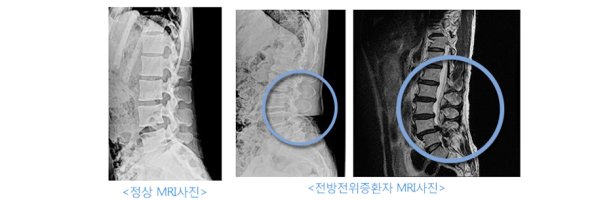

앞으로밀려나온상태를 척추 전방전위증이라합니다 척추분리증은 척추전반전위증을많이동반하게되는데정도가심하지않으면추나요법으로치료가가능합니다 .단밀려나온뼈는완전히제자리를...

척추 전방 전위증은추나요법이나약물요법으로도치료가되나 척추 분리증으로인한전방전위증은분리증에의하지않은전방전위증에비해서치료가어렵습니다. 일단은본원에서의전방전위증 환자의...